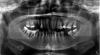

Messor Опубликовано 9 ноября, 2012 Автор Поделиться Опубликовано 9 ноября, 2012 вот оптг.речь идет о попытке сохранения 46, 47, 48 зубов. есть подозрения, что после удаления 46 распрощаемся в скором времени со всеми молярами. тем более пациент хорошо мотивирован на попытку сохранения зубов. какие еще возможны варианты лечения? Ссылка на комментарий

IvanK Опубликовано 9 ноября, 2012 Поделиться Опубликовано 9 ноября, 2012 Подвижность у зубов есть?Я сомневаюсь в эффективности лечения данных зубов. Это лечение ради лечения.Но если Вы вдруг все таки будете "играть в эту игру", для начала необходимо решить вопросы: терапевтическая санация с восстановлением полноценных контактных пунктов, идеальная гигиена, правильное распределение нагрузки. И еще вопрос, что будет дальше? Ортопед возьмет эти зубы под коронки?? Есть ли смысл в 48? Каков план протезирования? ИМХО Ссылка на комментарий

Bier Опубликовано 9 ноября, 2012 Поделиться Опубликовано 9 ноября, 2012 одностеночный дефект - вообще без шансов. Зато реальные шансы удалить это, аугментировать провал и поставить 2 имплантата пока кость есть. 5 Ссылка на комментарий

Аслан Опубликовано 13 ноября, 2012 Поделиться Опубликовано 13 ноября, 2012 извините, но тут максимально благоприятный прогноз будет только при своевременном удалении. хоть для съема, хоть для имплантов лучше будет с объемом кости. чем без него. при открытом кюрретаже вы его однозначно потеряете, сколько бы вы ни присыпали. единственное что может быть с вероятностью 80% поможет это эмдогейн на 37. все остальное бессмысленое занятие для пациента. а для вас клинический опыт. зачем сохранять 8ки? верхнюю? разъедините пломбы между 25и 27и вы получите подвижность в 27. 46 имхо вообще без вариантов. ну и самое главное. снимок у нас двухмерный, но судя по нему резорбция по фуркации есть. сколько ее глубина?? даже если вы ее "откроете" пациент при огромном желании никогда не вычистит там сам ни ершиками ни еще какой-то другой приспособой типа суперфлосса.14тдавно пора было убрать. 16 зачем? затронута фуркация, там даже вы не вычистите. 17 аналогично. 45 куда "выехал"? его укоротить коронкой или задвинуть ортодонтически миниимплантами, и коронку, тогда он еще нормальек постоит..прежде чем что-то оперировать проведите терапевтически все, закрытым кюрретажем, научите чистить, посмотрите два месяца за ним. если он не сможет это сохранить на два-4 месяца, то ни о какой хирургии и речи быть не может, только удалить. Ссылка на комментарий